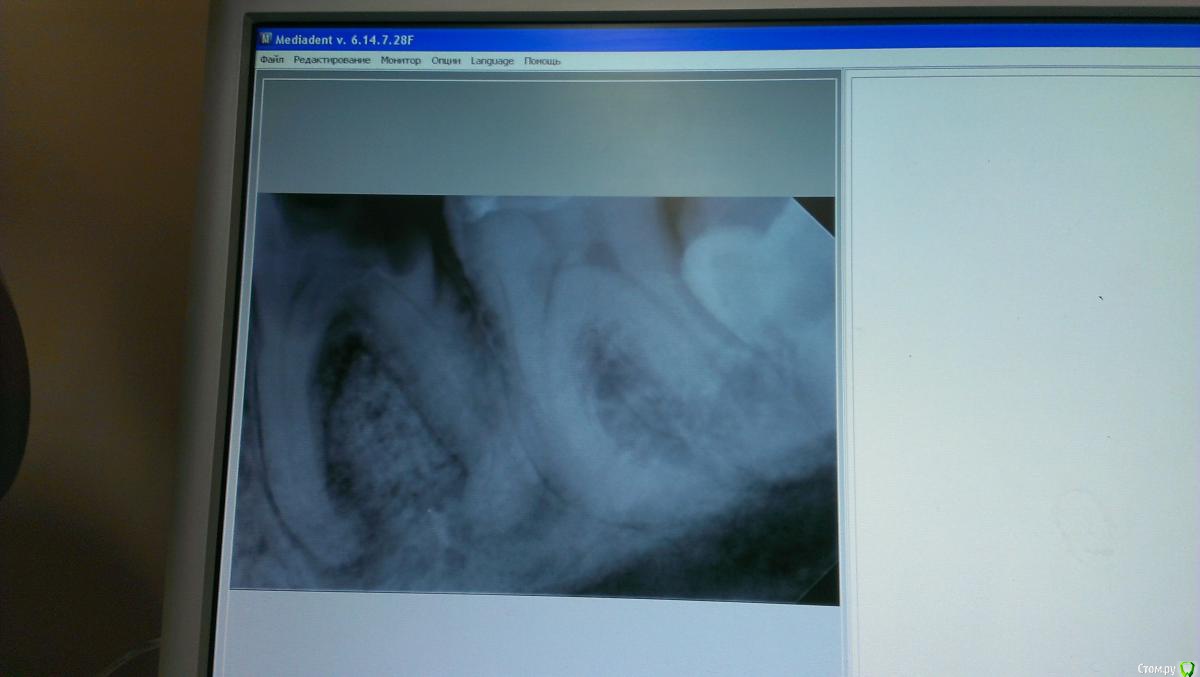

marialera Опубликовано 11 марта, 2015 Поделиться Опубликовано 11 марта, 2015 Пациент пришел с острой болью,год назад начал лечить этот зуб,положили ему на устья каналов мышьяковистую пасту,ватку и закрыли химическим композитом,сказали прийти через две недели,но он не пошел.Пришел уже ко мне,вот,говорит год прошел,болит очень.Сняла старую пломбу,под ней ватка,большое количество гнойного содержимого с кровью..Снимок,конечно,не очень качественный получился,но,вроде видно.Может стоит такой зуб удалить? Ссылка на комментарий

Girl Опубликовано 10 июня, 2015 Поделиться Опубликовано 10 июня, 2015 А что вы здесь скажите? Лечить? Если кто такое лечит, поделитесь прогнозом. Разряжение в бифуркации Ссылка на комментарий

St. Опубликовано 10 июня, 2015 Поделиться Опубликовано 10 июня, 2015 Этот удалять. По снимку это не получится нормально восстановить, и с дном пульпарной полости там беда. Ссылка на комментарий